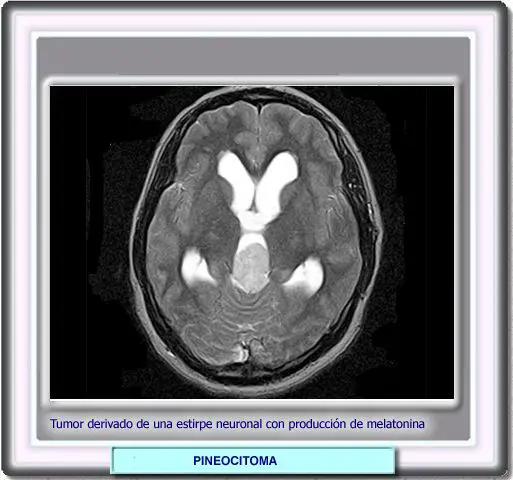

PINEOCITOMA

Los tumores de la glándula pineal pueden ser de varios tipos:

los que derivan de las verdaderas células pineales productoras de melatonina, que de acuerdo con su grado de diferenciación, se pueden clasificarse como pineocitomas y pineoblastomas (más malignos). Ambos tipos de tumores dan positiva las reacciones inmunoquimicas a la proteína S, la sinaptofisina y a la NSE.